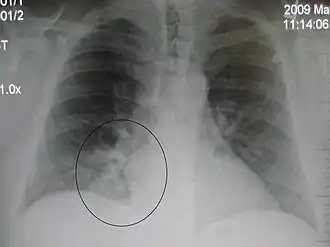

Right upper lobe pneumonia as marked by the circle. -

Left upper lobe pneumonia with a small pleural effusion.